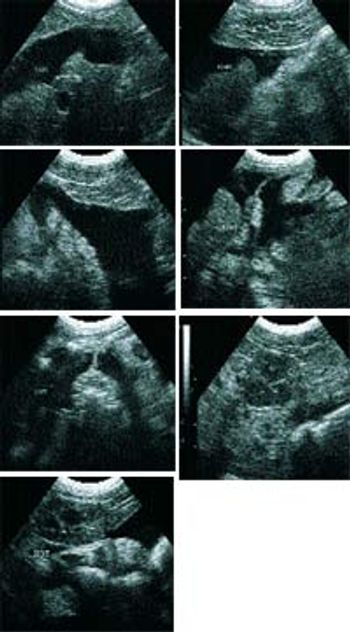

Q. Could you provide a brief review of hemoabdomen and its diagnosis/management in dogs and cats?

Q: Could you review pancreatitis and its diagnosis in dogs and cats?